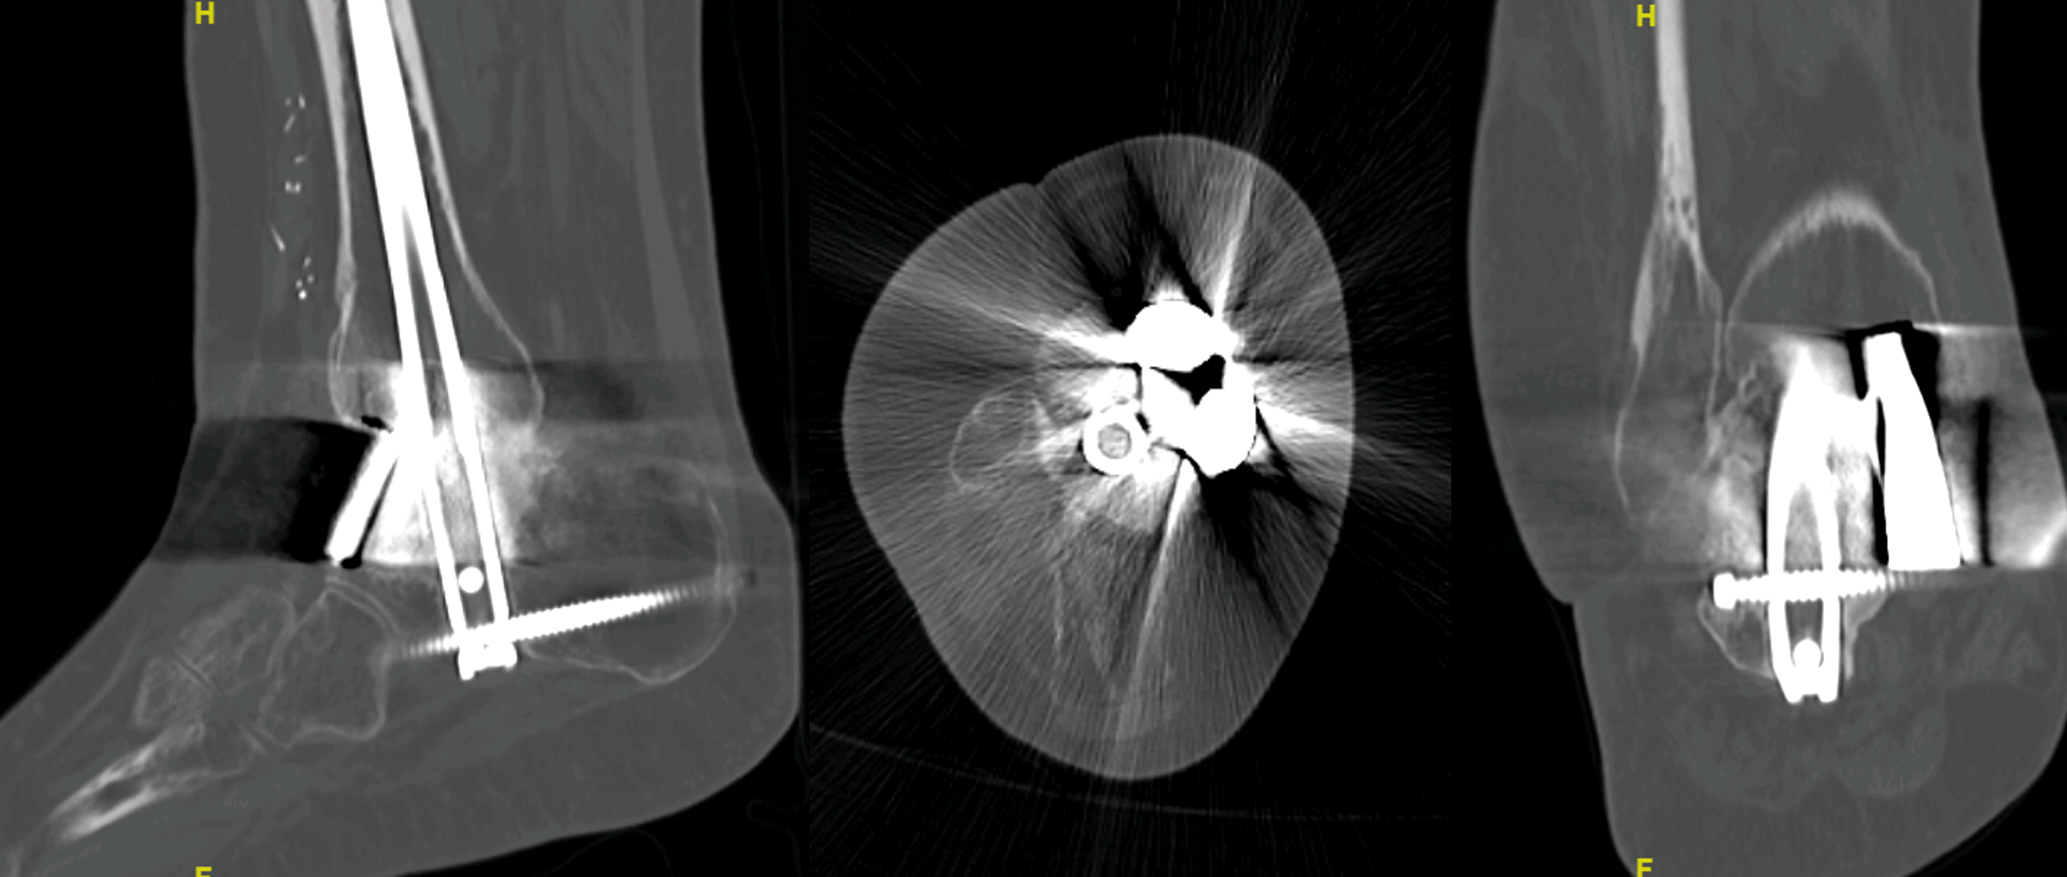

Total fusion was seen in the 1-year follow-up CT scan control, and a correct axis may be seen in X-rays, with no significative leg-length discrepancy (Figs. 3 and 4).

https://jbji.copernicus.org/articles/10/419/2025/jbji-10-419-2025-f04

Figure 4In spite of the image distortion due to radiolucent osteosynthetic material, signs of consolidation and the absence of indirect signs of pseudoarthrosis can be noted in the 1-year control CT scan of one of the patients (Case 2). This image, along with a painless weight-bearing ambulation, is enough to consider a consolidation of the defect.